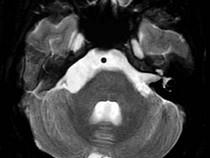

男,42岁,右侧听力下降,MRI检查如图,最可能的诊断为()A.表皮样囊肿B.听神经瘤C.三叉神经瘤D.脑膜瘤E.脑梗死

问题 男,42岁,右侧听力下降,MRI检查如图,最可能的诊断为()

选项 A.表皮样囊肿 B.听神经瘤 C.三叉神经瘤 D.脑膜瘤 E.脑梗死

答案 A